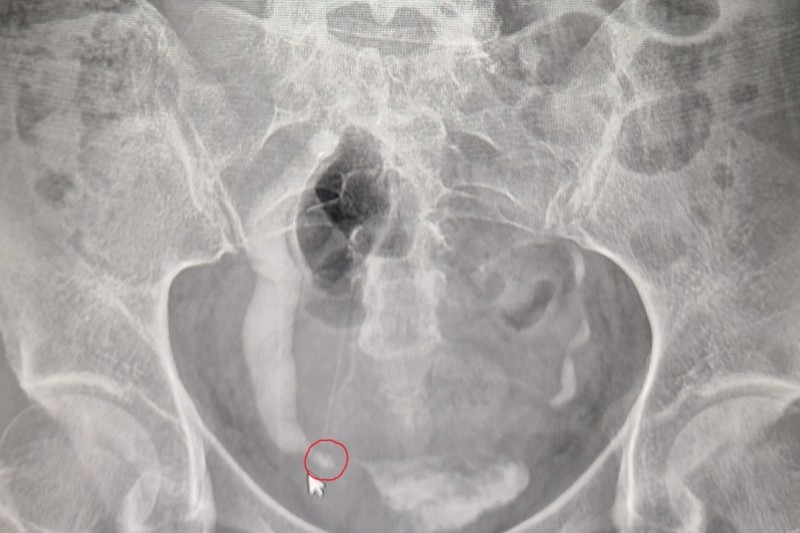

요로결석 진단방법 - 요로결석 원인과 증상, 치료방법

갑작스러운 극심한 통증 혹은 혈뇨의 경우에 요로결석을 의심합니다.

검사는 대부분 CT촬영으로 합니다. 갑작스럽게 통증으로 응급실에 오셨다거나 진료실에 오시면 바로 찍는 경우가 많습니다.

요로결석에 돌을 보는 CT는 금식하고 거창하게 찍는 이런 조형 CT보다는 비조형 CT로 바로 찍어볼 수 있습니다.

굉장히 간단하고 빨리 찍을 수 있고 비용도 비교적 저렴하고 엑스레이는 1~4장 정도밖에 찍지 않기 때문에 방사선 노출도 적습니다.

그래서 결석 CT는 크게 부담스러워하지 않으셔도 됩니다. 이전에 말씀드렸던 무증상 신장 결석은 CT보다는 보통 우리가 건강검진 초음파를 진행하면서 많이 발견이 됩니다.

그래서 초음파에서 결석이 보이면 추가적인 검사 혹은 치료방침을 결정하기 위해서 또 추가적으로 CT를 찍어서 도대체 결석이 몇 개인지, 몇 mm, 몇 cm인지 크기는 어떻게 되는지, 위치는 어떤지, 이런 부분을 면밀히 검사합니다.

가장 중요한 진단방법은 CT이고 초음파나 엑스레이는 보조수단이 될 수 있습니다. 또 소변검사에서 혈뇨가 좀 보일 경우 소변검사도 도움이 됩니다.